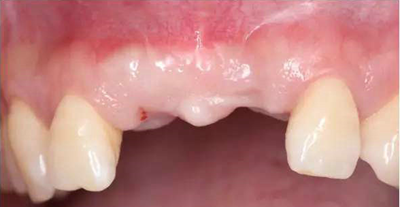

患者33歲,女性,主訴4個(gè)月前因外傷拔除上11、21牙,未行活動(dòng),固定義齒修復(fù),現(xiàn)因影響美觀要求種植修復(fù)。11,21牙缺失,缺牙區(qū)牙齦狀況良好,無潰瘍紅腫,厚齦型,口腔衛(wèi)生較好,無明顯牙齦退縮。

過渡義齒制作完成及試戴

過渡義齒佩戴3個(gè)月后